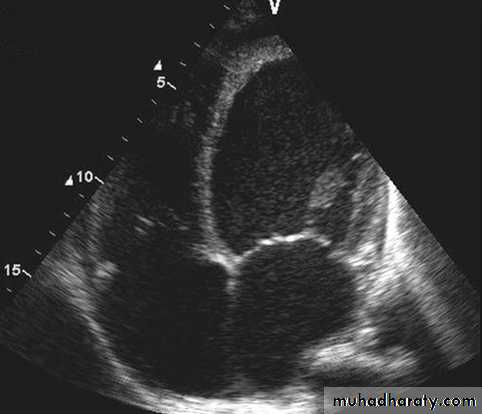

Echocardiogram: Chamber enlargement and global hypokinesisCXR

ECHO